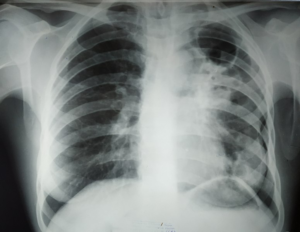

Рентгенологическая картина

При пневмонии предпочтительно выполнение рентгеноскопии, на снимке которой определяется стадия поражения легких с локализацией очага воспаления. Тени на снимке достаточно размыты, а пораженный участок легкого как будто задымлен.

Основным способом определения туберкулеза является флюорография и крайне редко рентгенография легких. На рентгеновском снимке границы очага воспаления четко очерчены, а тени расположены преимущественно в одном легком (средней или в верхней доле).